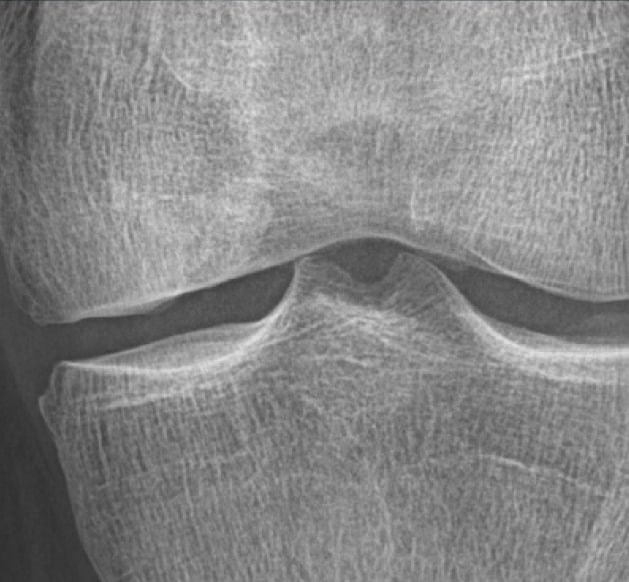

11 years postoperatively

The patient is symptom-free